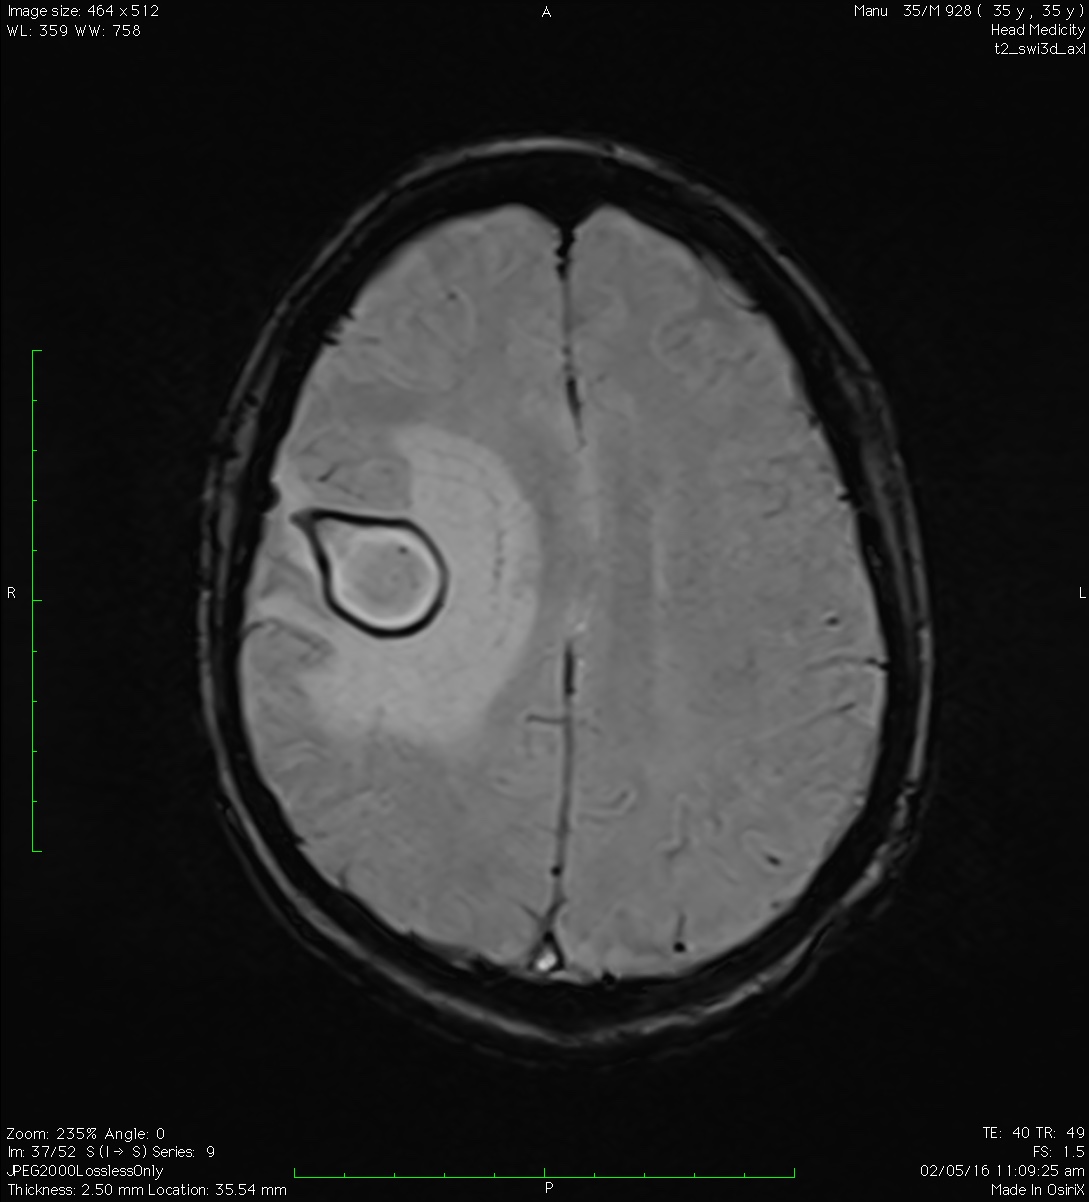

Bei bakterieller Gehirnhautentzündung treten fast immer starke Kopfschmerzen auf. Es handelt sich dabei um eitrige Pickel oder Entzündungshöhlen, die häufig unter der Haut . Bei einer Meningitis kommt es zu einer Entzündung der Hirnhäute, die das Gehirn wie eine Schutzhülle umgeben. Überblick über . Kann der Abszess operativ entfernt werden, ist der Verlauf günstig einzuschätzen.Der Hirnabszess ist eine örtliche Infektion des Hirngewebes, bei der sich innerhalb einer Bindegewebskapsel eine Eiteransammlung bildet. Ursache der Eiteransammlung ist eine Entzündung. Das Wichtigste in Kürze: Bei einem Hirninfarkt kommt es zu einer Unterbrechung des Blutflusses in einem hirnversorgenden Blutgefäß.

Kurzübersicht. Krampfanfälle: Häufig kommen Krampfanfälle und neurologische Störungen hinzu, die auf einen intrakraniellen Herd schließen lassen.Breitet sich die Sinusitis ins Gehirn aus, ist meist eine Meningitis die Folge. Die Behandlung erfolgt mittels chirurgischer . Symptome: Sehr vielfältig, unter anderem: Rötung, Schmerzen, Schwellung. Die Symptome eines Gehirnabszesses können sich schnell oder langsam entwickeln; sie äußern sich in der Regel in Form von: Kopfschmerzen – die oft schwerwiegend sind, sich in einem einzigen Abschnitt des Kopfes befinden und nicht mit Schmerzmitteln gelindert werden können. Schwierigkeiten bei der Bewegung.Bei klinischem Verdacht auf einen Hirnabszess ist der wichtigste diagnostische Schritt die kraniale/zerebrale Bildgebung.Die zentrale Nekrose des Abszesses zeigt in T1 . Risikofaktoren. Der Hohlraum ist durch einen Entzündungsprozess entstanden, in dessen Verlauf er von Bindegewebe begrenzt wird und kann überall im Körper auftreten.jeder, der von einer solchen Problematik betroffen ist, kann unter erhöhtem Hirndruck leiden. Dazu zählen beispielsweise hohes Fieber, Kopf- und Gliederschmerzen, Übelkeit und Erbrechen. Ein chronischer Hirnabszess entwickelt sich langsam, häufig kommt es währenddessen zu Krampfanfällen, halbseitigen Lähmungen oder Halbseiten . Epileptische Anfälle.

Medizinwissen, auf das man sich verlassen kann

Die Symptome werden durch eine Kombination aus Infektion, Hirngewebeschädigung und Druck auf das Gehirn verursacht, da der Abszess wächst und mehr Platz einnimmt. Da eine Unterscheidung zwischen Abszess und hirneigenem Tumor oder Metastasen mittels kranialer Computertomografie meist nicht möglich ist, wird bei Verdacht auf einen Hirnabszess . Parasiteninfektionen des Gehirns. Abszesse gehören zu den Leiden, die als äußerst unangenehm empfunden werden. Die Symptome eines Hirninfarkts treten sehr plötzlich auf und können sehr . Ein Hirnabszess ist höchstwahrscheinlich auf eine bakterielle oder Pilzinfektion in einem Teil des Gehirns zurückzuführen.

Kurzinformationen: Hirnabszess

Aufgrund der möglichen Komplikationen, die auftreten können, sollten Patienten mit Symptomen, die auf einen Hirnabszess hindeuten, so schnell wie möglich eine Notaufnahme aufsuchen, um eine spezialisierte Untersuchung durchführen zu lassen.Fieber entwickelt sich bei der akuten tuberkulösen Meningitis im Verlauf einer Woche. Im weiteren Verlauf gesellt sich eine schmerzhafte Nackensteifigkeit (Meningismus) hinzu. CT oder MRT mit und ohne Kontrastmittel sind die diagnostischen Methoden der Wahl.Die häufigsten Symptome sind Kopfschmerzen und Fieber, bei manchen Menschen kann es auch zu Übelkeit und/oder Erbrechen kommen. Meningitis oder ein Hirnabszess können sich entwickeln. Der Hirnabszess ist eine Form der eitrigen Reaktion mit Gewebseinschmelzung und Kapselbildung, die in der Mehrzahl der Fälle hämatogen-metastatisch oder fortgeleitet, am häufigsten bei Otitis, Sinusitis und Mastoiditis, entsteht. Diagnostik: Untersuchung der betroffenen Körperregion; bei Bedarf . Unspezifische Krankheitsanzeichen wie Bauchschmerzen, Übelkeit, Missempfindungen und Veränderungen des Stuhlverhaltens treten bei einem Drittel der Patienten auf. Bildet sich ein Abszess in der Haut, macht sich dies durch eine gerötete und schmerzhafte . Symptome (Auszug) Kopfschmerzen. 80%) ist der Kopfschmerz, dieser ist oft das einzige Symptom. Häufig zu finden sind Kopfschmerzen, Anfälle, Erbrechen und Übelkeit. Geht ein Abszess mit einer Entzündung einher, kann man folgende Symptome feststellen: Rötung. Gehirnentzündung (Enzephalitis) Intrakranieller epiduraler Abszess und subdurales Empyem. Symptome können beinhalten Kopfschmerzen, Lethargie, Fieber und fokale neurologische Defizite. Sie entsteht, wenn Krankheitserreger in den Körper eindringen.Unter einem Abszess versteht man eine Eiteransammlung in einem Hohlraum. medikamentöse Therapie. Nur 10 % der Hirnabszesse werden durch offene Schädel-Hirn-Traumen oder . Diese Eiteransammlung liegt meistens unter der harten Hirnhaut, der Dura mater (subdural), sie kann aber auch oberhalb der harten Hirnhaut lokalisiert sein (epidural). Nur 40–50% der Patienten zeigen erhöhte Temperaturen, die bei Abszessen in anderen Körperregionen ein führendes Symptom sein können [1, 2]. Die Diagnose wird mithilfe einer Kontrastmittel-MRT, oder falls nicht verfügbar, einer Kontrastmittel-CT gestellt.Die Symptome bei Subduralempyem sind Fieber, Erbrechen, Bewusstseinsstörungen und schnelle Entwicklung von neurologischen Anzeichen einer weitausgedehnten Beteiligung einer Hirnhemisphäre. In zwei Dritteln der Fälle bleiben die Symptome bis zu zwei Wochen bestehen, bevor die . Ein Hirnabszess ist eine intrakranielle Eiteransammlung. Die Sterblichkeit liegt bei 5 bis 15 Prozent der Betroffenen. Bei den unterschiedlichen Formen der Gehirnhautentzündung (Meningitis) sind die Symptome und Beschwerden in ihrer Entwicklung und Ausprägung verschieden.Neben Symptomen, die durch die bakterielle Infektion erklärt werden können, wie ein geschwächter Allgemeinzustand und Fieber , kann bei einem Abszess im Bereich der Mandeln auch Schluckbeschwerden sowie eine sichtbare Rötung im Rachenbereich auftreten.